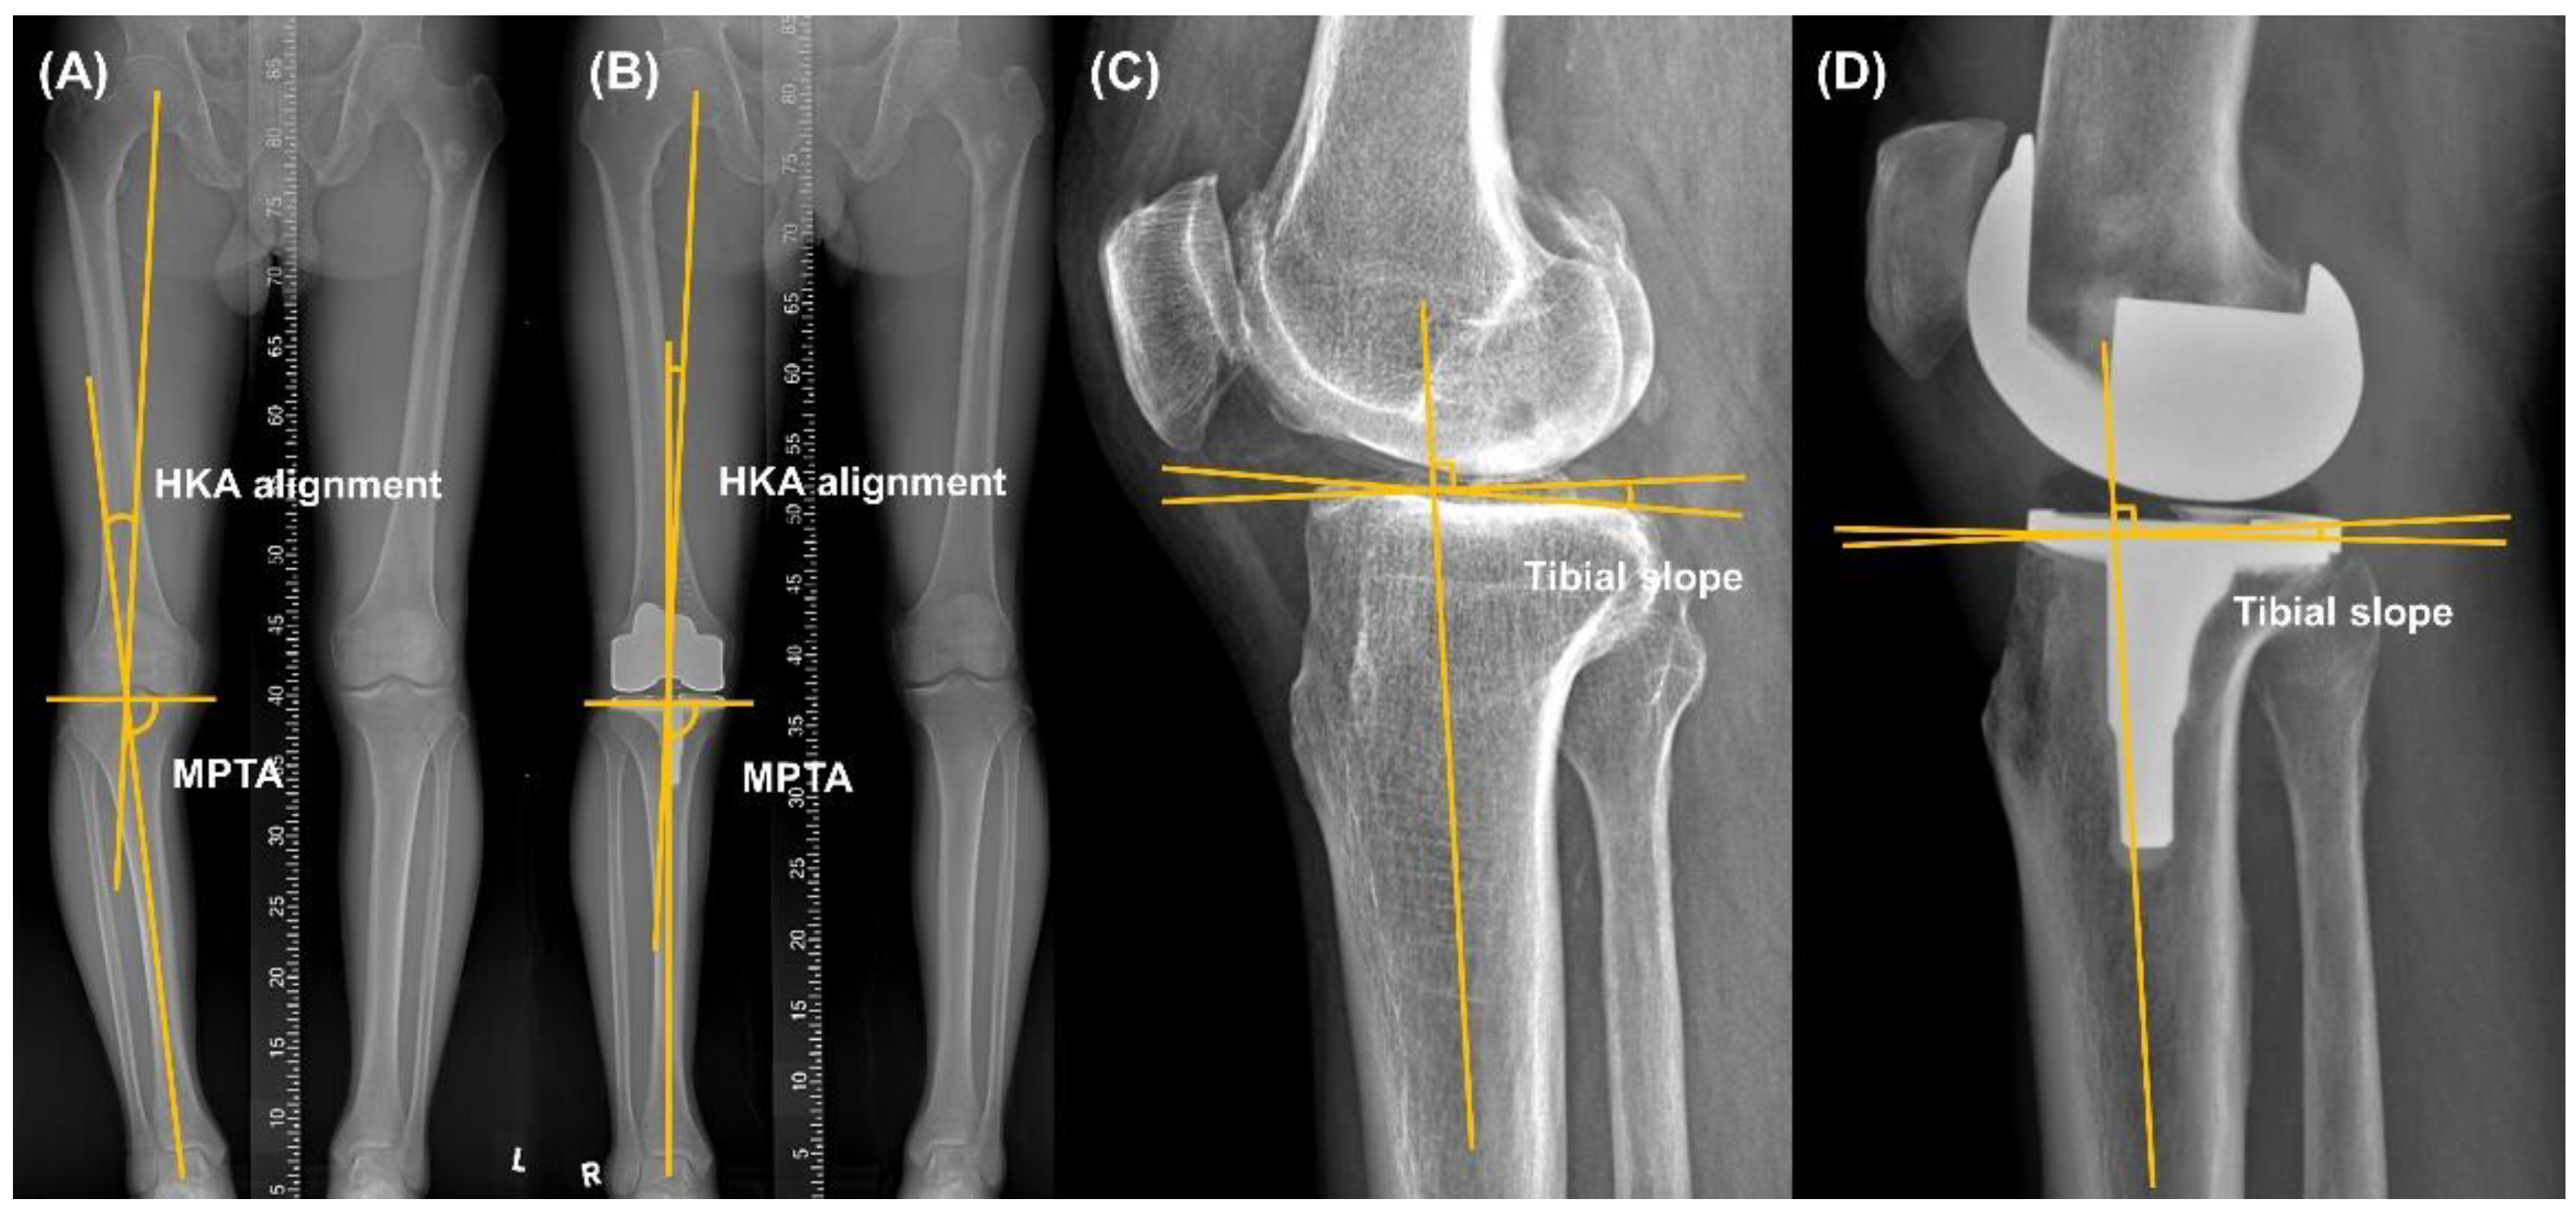

2.2. Radiographic and Clinical Assessment

| Pre-Operation | Post-Operation | p Value | |

|---|---|---|---|

| HKA alignment, ° | 10.4 ± 6.4 | 1.9 ± 1.7 | <0.001 |

| MPTA, ° | 83.9 ± 3.3 | 90.1 ± 0.9 | <0.001 |

| Tibial slope, ° | 9.3 ± 4.4 | 3.2 ± 2.1 | <0.001 |